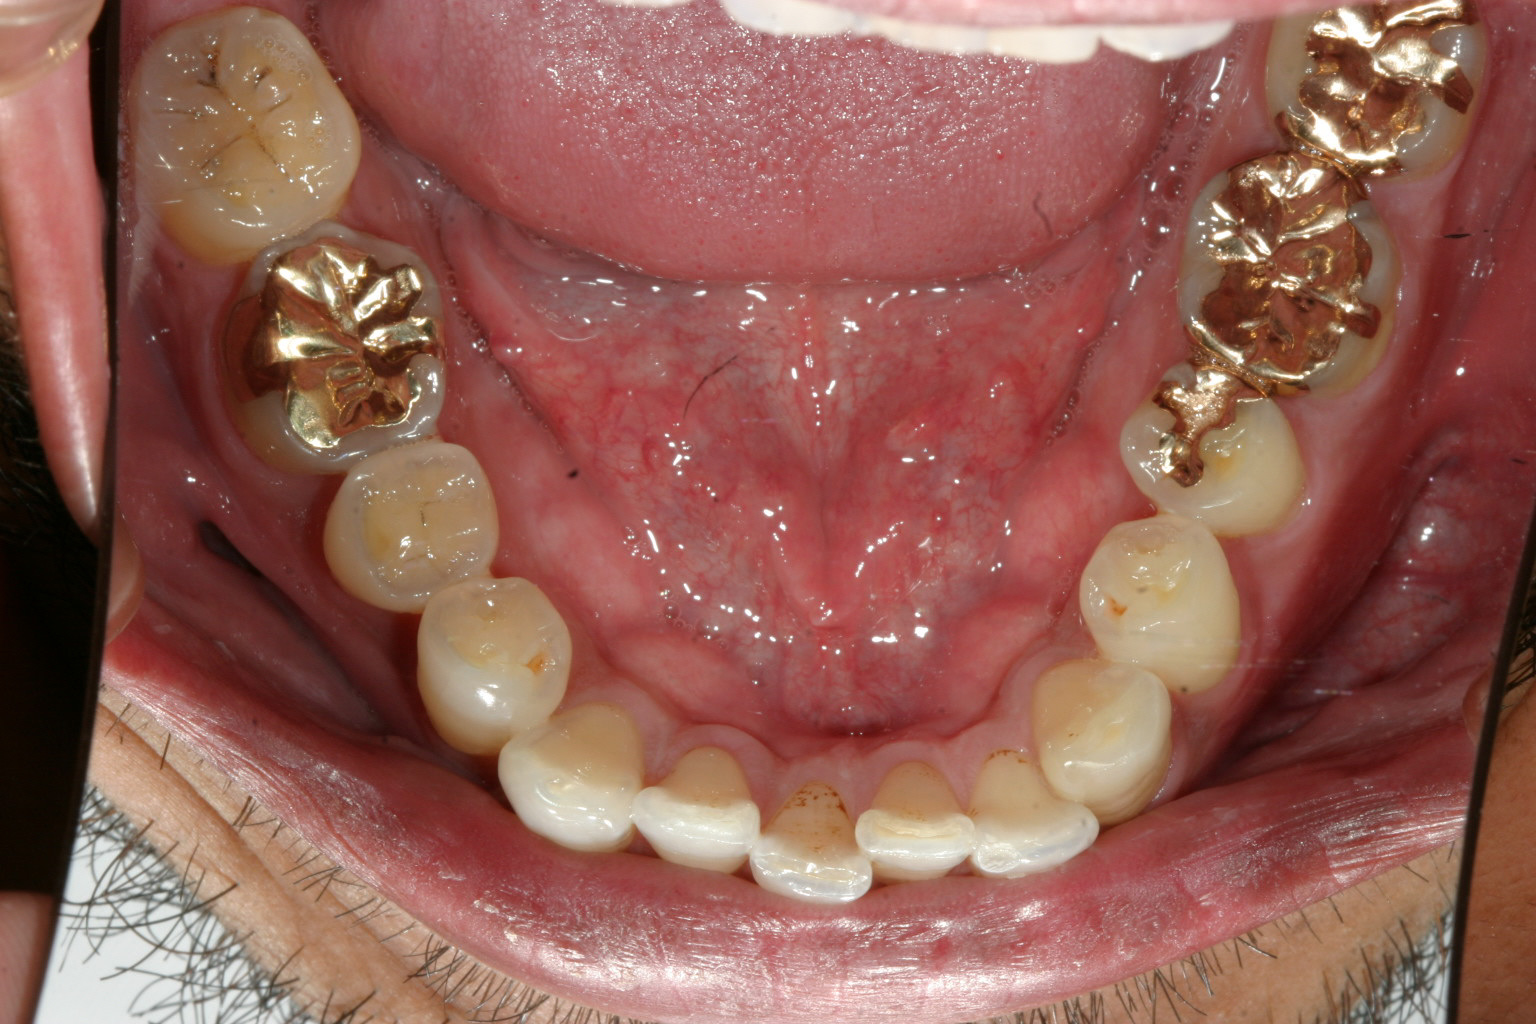

綺麗に並んでます。

側面観も綺麗になりました。

この症例は右側臼歯を後ろに順番に下げる事により犬歯が入るスぺースを確保しました。

後ろに下げる行為を遠心移動と言いますが、これをインビザライン矯正で行うのはかなり患者様にとって根気のいる仕事で臼歯部でしっかりチューイと言われるホースをしっかり噛んで頂かないとなかなか上手く行かない治療法です。

今回は加速矯正装置PBMを使用する事により短期間で完了しました症例です。